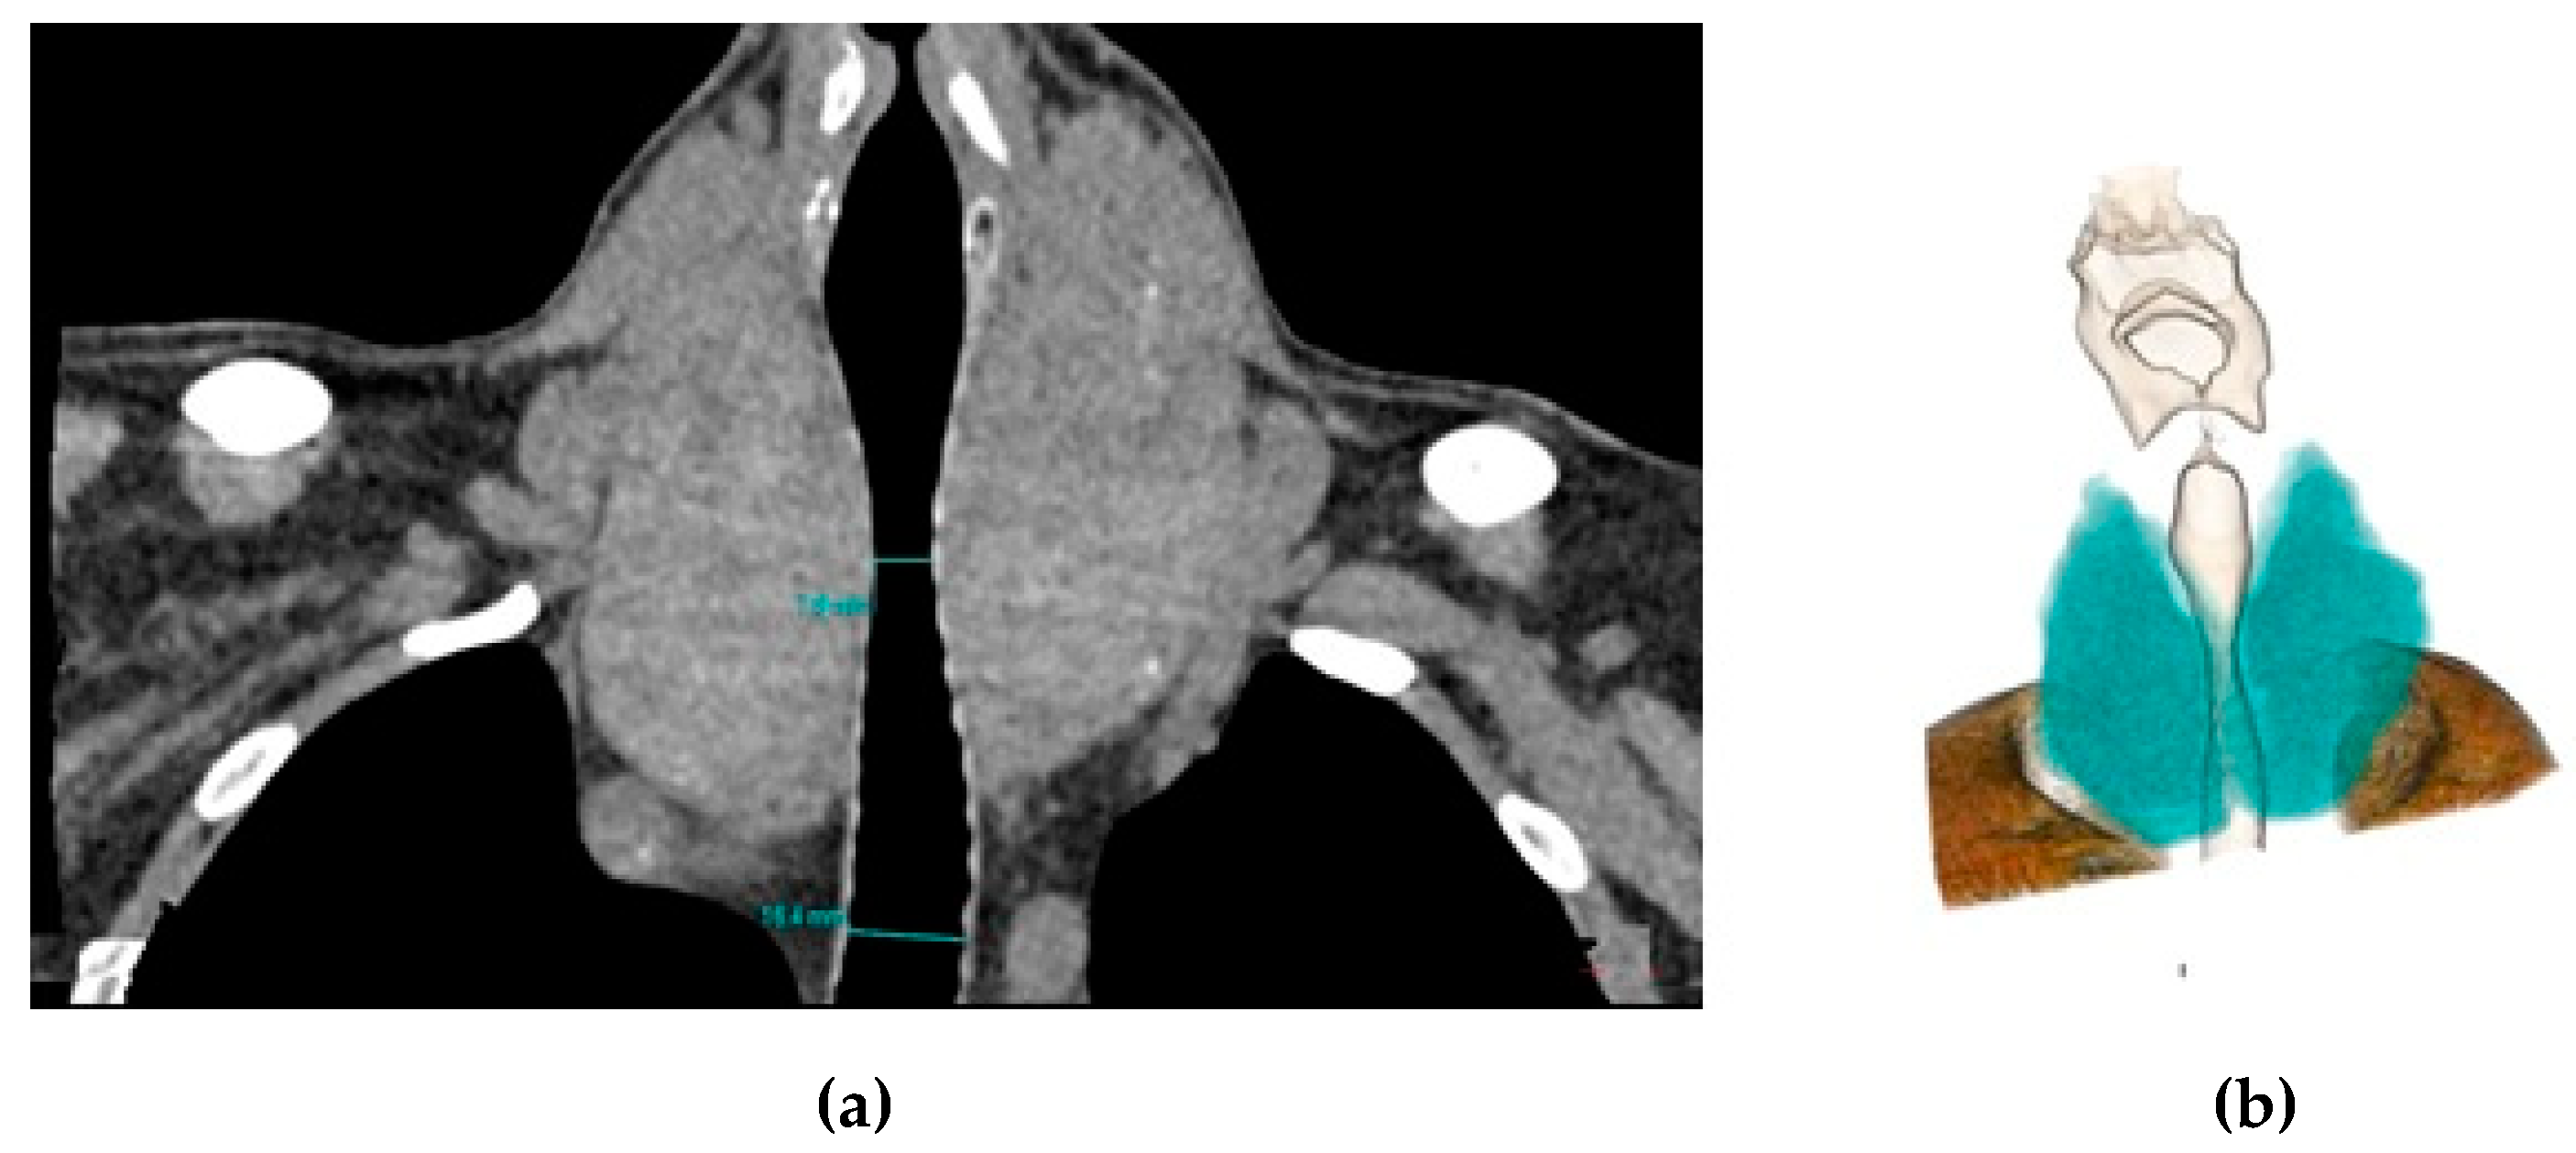

2.2. Radiological Analysis

2.2.2. Image Evaluation